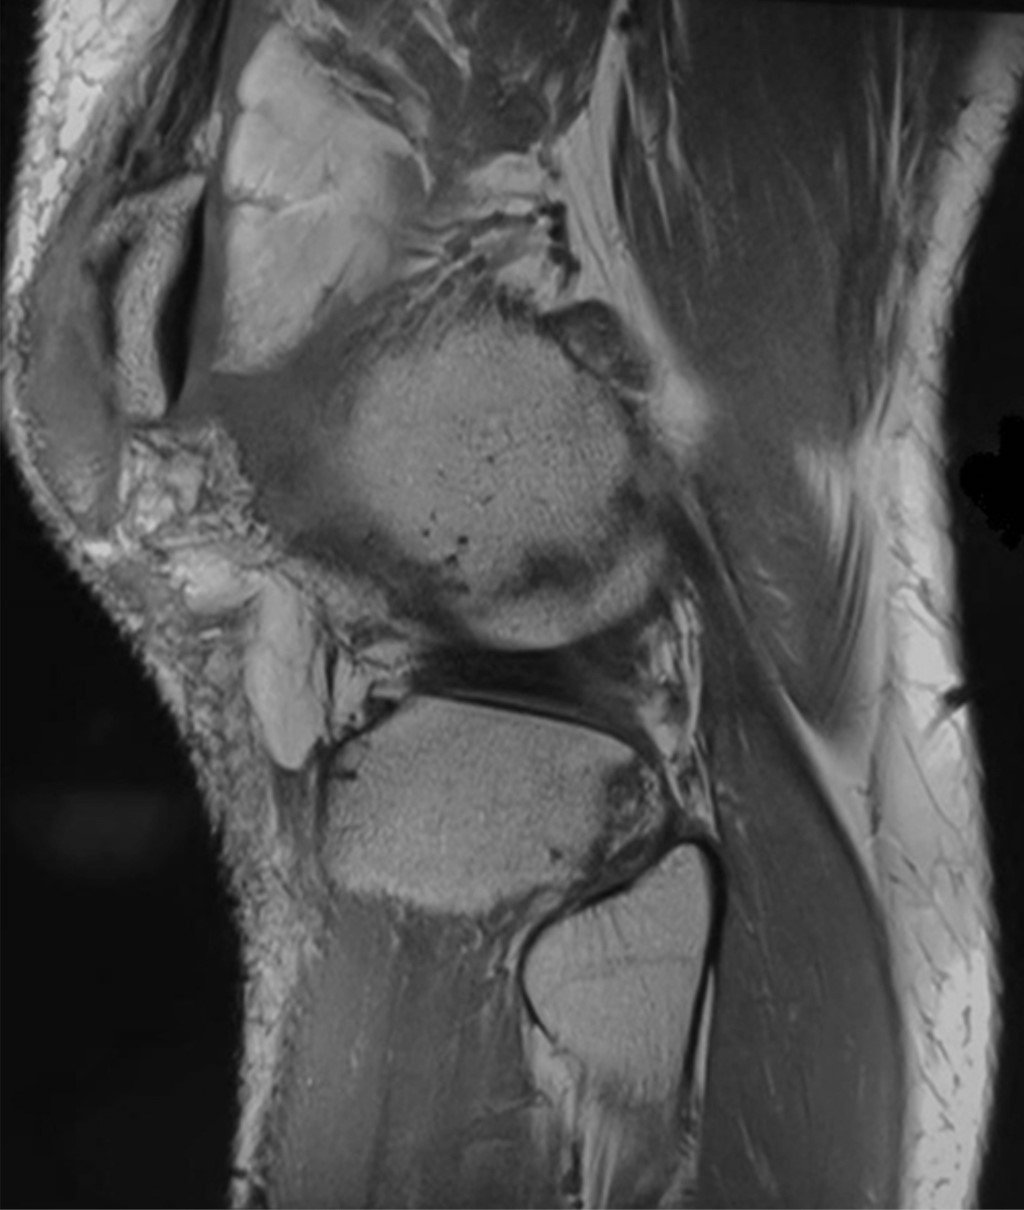

Masculino de 22 años que sufrió accidente de alta velocidad en motocicleta al viajar como pasajero. Al examen físico de la extremidad pélvica izquierda encontramos luxación expuesta de rodilla izquierda, sangrado abundante, daño a tejidos blandos, a la exploración vascular con Doppler detectamos un índice tobillo-brazo de 1.0 y la exploración neurológica no fue valorable. El paciente inicialmente es tratado en urgencias con protocolo de control de daños, se coloca fijador externo, lavado quirúrgico más desbridamiento mecánico y químico. Durante el procedimiento se detecta ruptura del tendón rotuliano, ligamento cruzado anterior, ligamento cruzado posterior, ligamento poplíteo, ligamento colateral lateral más fractura de cóndilo medial y lesiones condrales en 60% de la superficie articular del cóndilo medial. La exploración del paquete vascular de la región poplítea sin lesión, con pulsos disminuidos. Se realizó ecografía Doppler de extremidad pélvica izquierda, la cual reporta: 1. Arteria poplítea permeable, con flujo de aspecto trifásico, 2. Arteria tibial posterior permeable, con flujo de aspecto trifásico, 3. Arteria tibial anterior permeable, con flujo de aspecto trifásico y 4. Arteria pedia permeable con flujo presente. La resonancia magnética de miembro pélvico izquierdo revela: lesión multiligamentaria en la rodilla más ruptura de tendón rotuliano (Figura 1).

Figura 1